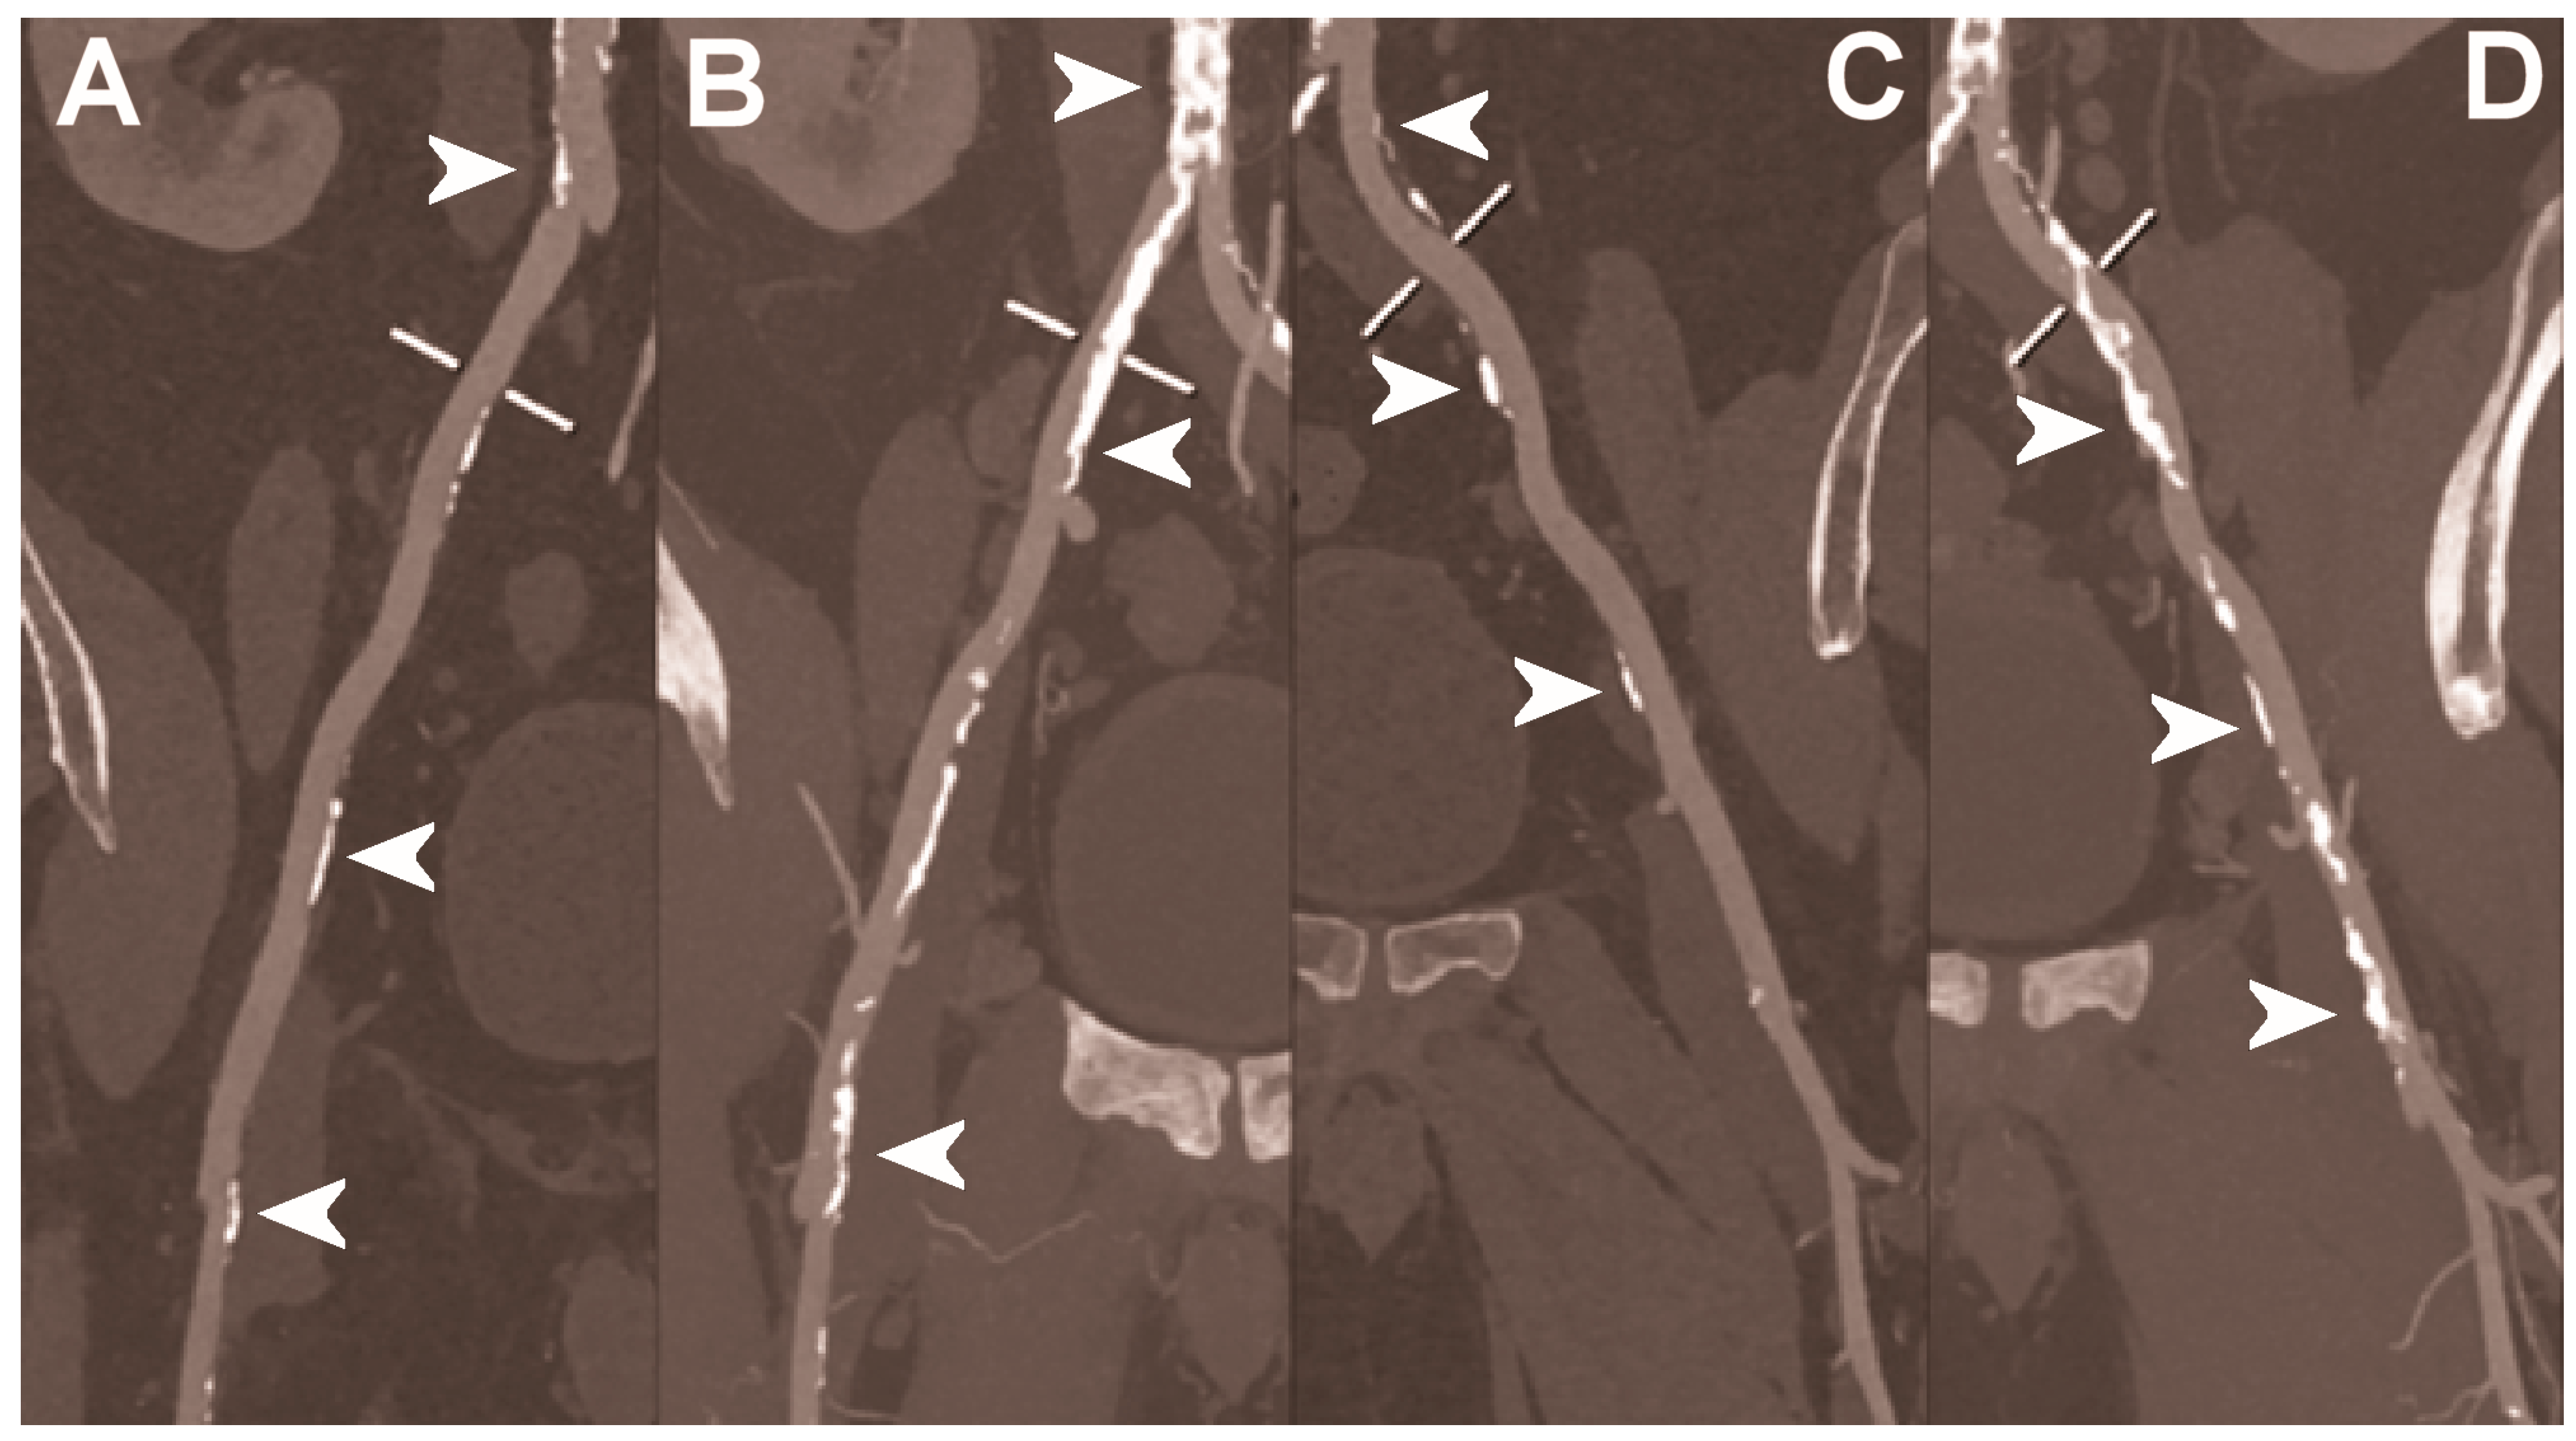

| Dangelmaier et al. 2018 [111] | In vitro phantom (abdominal aortic aneurysm phantom filled with iodine, gadolinium, or calcium). | Ability of PCCT in combination with a dual contrast agent injection to capture endoleak dynamics and effectively distinct leaking contrast media from intra-aneurysmatic calcifications, thereby allowing for a significant reduction of radiation exposure. |

| Sigovan et al. 2019 [112] |

|